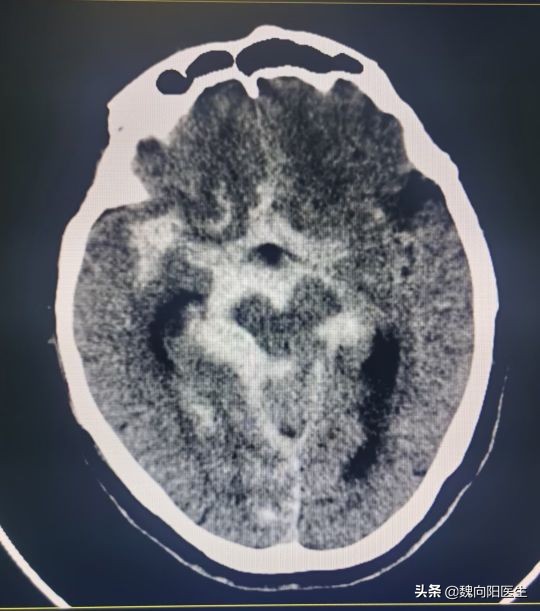

赶紧拉到医院,头CT提示:蛛网膜下腔出血。

正常人的脑积液属于无色透明的,蛛网膜下腔出血之后,血液涌到脑室里面和蛛网膜下腔,与脑积液混合就会变成血红色。

脑脊液充满于大脑的表面、侧脑室、第四脑室、第三脑室、椎管内脊髓的表面和腰椎管内。